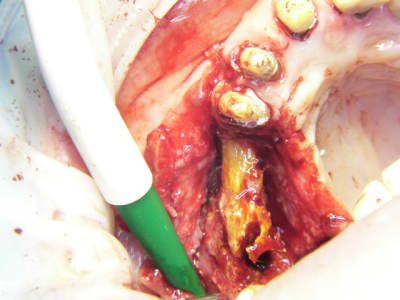

bon et bien ça c'est fait!

curetage (deux bonnes heures) dépose des deux vis d'ostéo et de l'implant en 16, nettoyage implant en 14/15 (axe un peu limite pour cause structure osseuse) et 17.

Vitalos

le greffon placé il y a 6 mois (grosse corticale) était dans le "vide" au niveau de 14, et il m'aurait fallu le piezzo éventuellement (il n'était pas installé, pour cette chir) pour "percer" la corticale sans pression, car à la fraise, je sentais le bloc plier, et nous avons préférés (avec le confrère) tenter un compromis pour la prothèse qui ne sera pas catastrophique et devrait permettre à la patient (qui a déjà subie 2 greffes, menton et ramique, avec un souvenir sympa du menton d'ailleurs)d'avoir une reconstruction fixe.

je ne sais pas si le vitalos permettra de rattraper ce cas là, mais vu tous les soucis que nous avons rencontrés pour le nettoyage (biooss infiltré dans la muqueuse de partout, j'ai du "virer" 60% du périoste et honnêtement je ne savais pas trop comment faire un "abri" de reconstruction pour l'os et l"environnement tissulaire, de façon simple.

photos montrant le hiatus greffe/os et pose avec vitalos à la fin